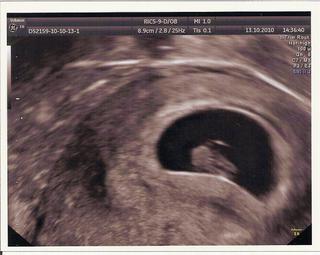

Holky, podávám hlášení. Květoškovi už krásně bilo srdíčko. Měří 14mm, odpovídá 7+5tt. Rozloučili jsme se s Machačem a tradá ke svému lékaři.